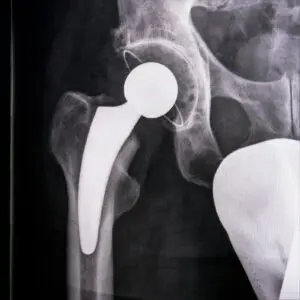

Разлика между коксартроза и остеопороза